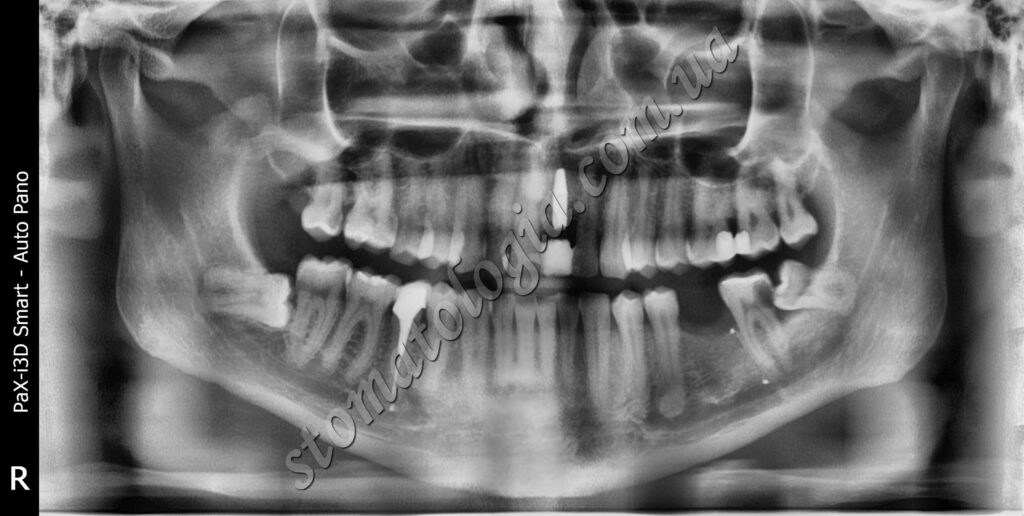

Ретиноване ікло верхньої щелепи спричинило запалення. Ретиновані також усі зуби мудрості